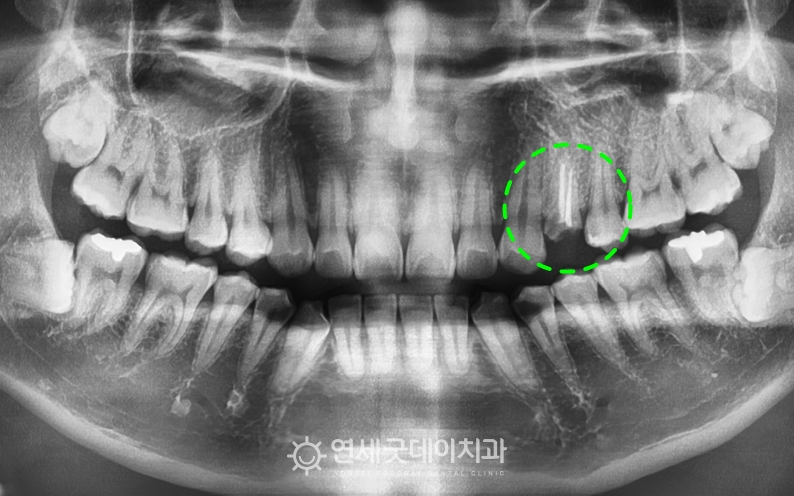

치아파절로 재신경치료 전 엑스레이

▲ 치료 전 엑스레이 (촬영시기 : 2025년 8월)

엑스레이를 보면, #24 부위에 치아파절이 관찰되며

과거 신경치료를 받았던 부위임이 확인됩니다.